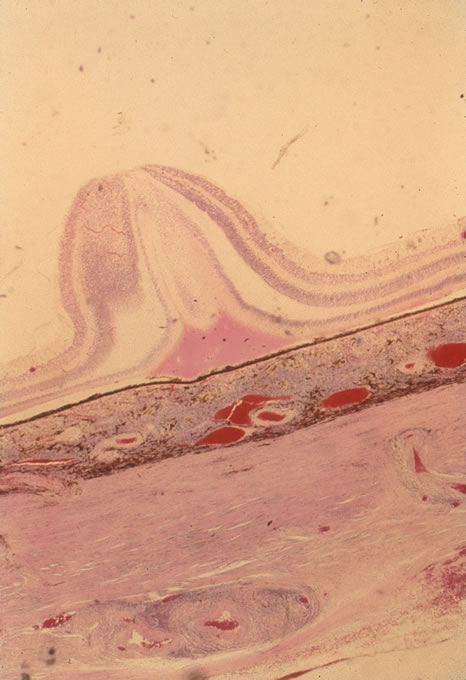

The incubation period for HSV is from 2 to 14 days. Primary infection with HSV type 1 is often asymptomatic but may produce oral, eye, or skin lesions (Fig. 1). In children younger than age 5, a painful gingivostomatitis or pharyngitis with fever and cervical adenopathy is the most common presentation. HSV type 2 infections usually involve the glans penis and penile shaft in men, and the vulva, perineum, buttocks, cervix, and vagina in women.1 Fever, malaise, anorexia, and tender inguinal adenopathy may accompany the typical vesicular skin eruption. The ulcerated lesions are exquisitely tender and may persist for several weeks before healing.

In primary ocular HSV infections, a severe follicular conjunctivitis with regional adenopathy is present. Vesicles may appear on the eyelid skin or lid margin, producing blepharitis (Fig. 3). Corneal involvement initially takes the form of a superficial punctate keratitis, which may progress to dendritic or geographic ulceration. Stromal infiltrates and uveitis are less common and relatively mild in primary disease. In uncomplicated cases, lesions usually heal completely in 2 to 3 weeks without scarring. Most cases of ocular HSV are recurrences. Recrudescent ocular herpes may take the form of dendritic or geographic ulcers, recurrent erosions, interstitial or disciform stromal keratitis, and anterior uveitis.3 HSV may also be an agent of retinitis and acute retinal necrosis (Fig. 4).